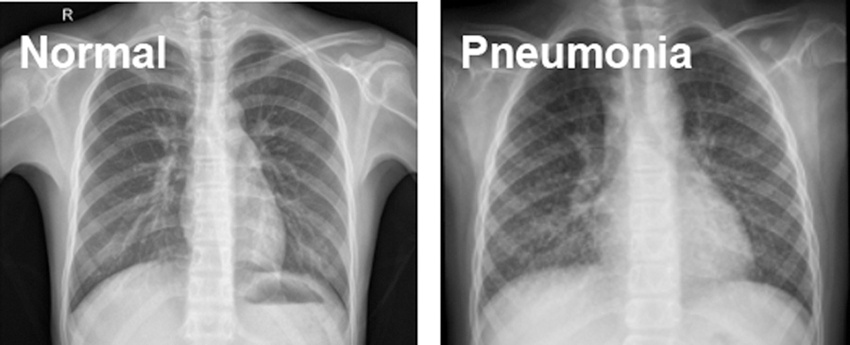

The source of data is Kaggle.com. Paul M-Kaggle dataset of chest X-ray images (Pneumonia) [19]. The network is fed with images of chest X-rays, as shown in Fig. 1. There are 5,856 images divided into two categories: Normal and Pneumonia, as shown in Table 1. Every chest radiograph was checked for quality control, and any scans that were subpar were discarded or indecipherable being discarded for further examination of CXR images and then graded by a physician before being fed into a deep learning network.

Figure 1: Normal and Pneumonia CXR images

The dataset’s image resolution ranges from 400 p to 2000 p; thereby, all images are scaled to a set size of 224 × 224 (standard choice) before feeding to the CNN because neural networks only take inputs of the same size and the smaller the image size, the better the model training.